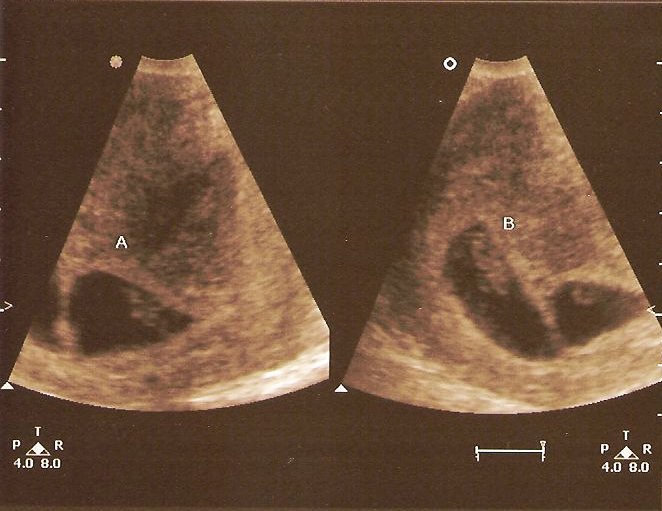

Regina had an appointment with the baby doctor at 8:00 AM yesterday. The nurse operating the ultrasound machine told us she would first look at the top of her stomach before looking at the babies closeup (at 8 weeks, they would be the size of kidney beans). Then she told us something we were not expecting, or prepared for. Regina is carrying TWINS!!!! Both of our jaws had to be picked up off the floor. My eyes were watering, and my head was spinning. The nurse then went in for a closer view to do the measurements, heart rate, etc. These pics are from the closeup view. Even at this small size we could easily see their heart beat. The twins are due November 29, 2007.